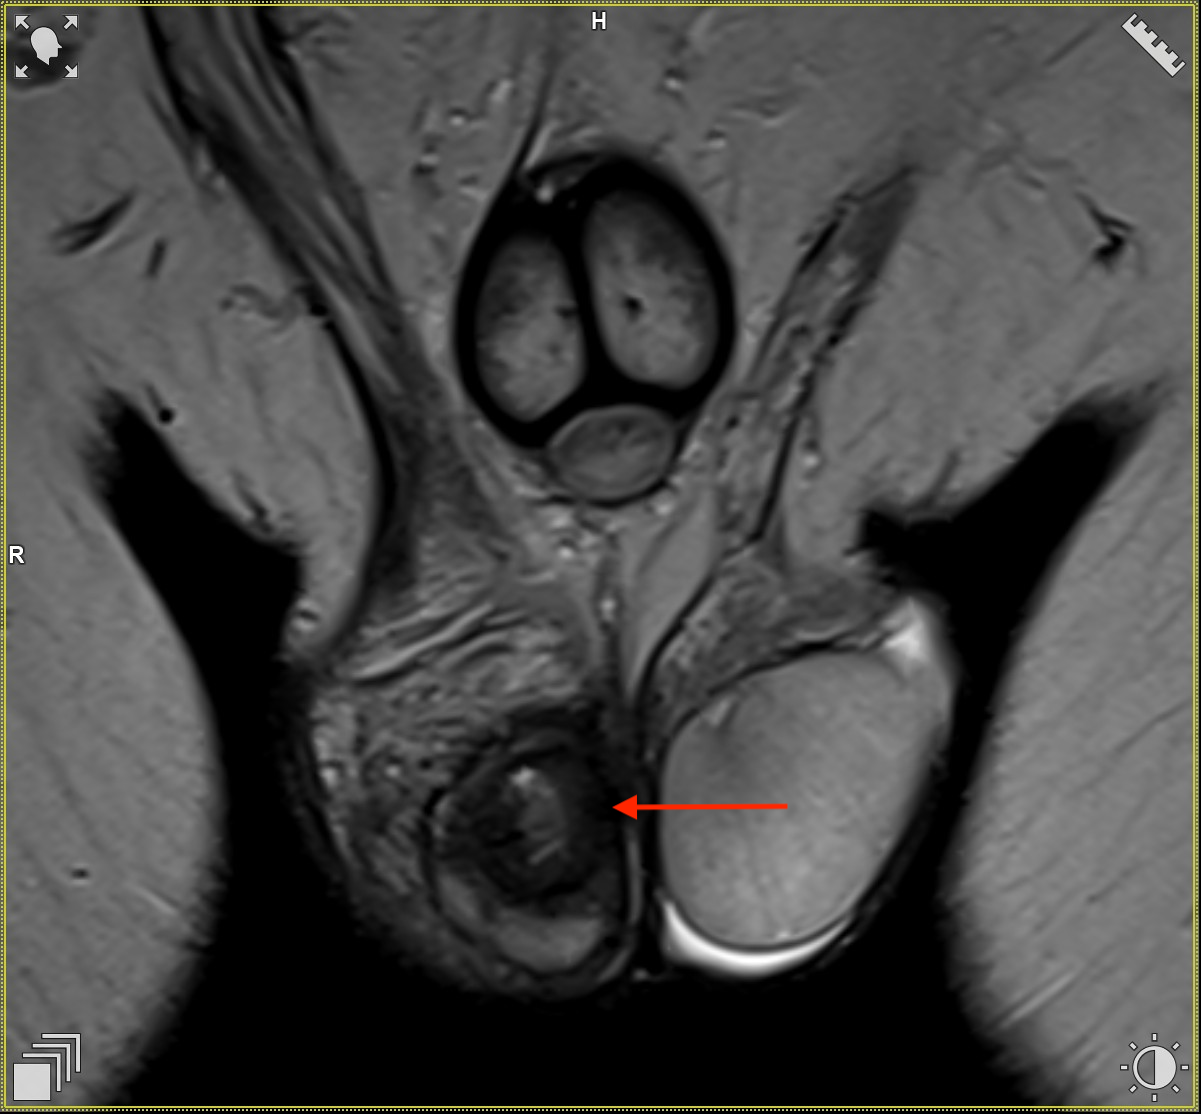

Obrazy w sekwencjach T2-zależnych w płaszczyźnie osiowej. Widoczna zmiana po-operacyjna w jądrze prawym.

Obrazy w sekwencjach T2-zależnych w płaszczyźnie czołowej. Widoczna zmiana po-operacyjna w jądrze prawym.

W kontrolnym USG po 3 miesiącach ponownie opisano litą zmianę w prawym jądrze, tym razem o wymiarach 15 × 15 mm, ale bez widocznego ukrwienia. Pacjent został ponownie skierowany na badanie MR jąder. W drugim badaniu opisano prawe jądro o wymiarach 20 × 21 × 38 mm, o nieregularnym kształcie. W części centralnej stwierdzono obszar o wymiarach 15 × 14 × 16 mm, z osłabionym sygnałem w T2, centralnym przejaśnieniem, silną restrykcją dyfuzji i wzmocnieniem kontrastowym na obwodzie – obraz w pierwszej kolejności sugerował ropień lub zmiany pozabiegowe po resekcji. W okolicy górnego bieguna, podtorebkowo, widoczne były drobne obszary płynowe do 6 × 3 × 3 mm. Płyn w osłonkach śladowy, najądrze niepowiększone, powrózki bez żylaków, węzły chłonne bez limfadenopatii.